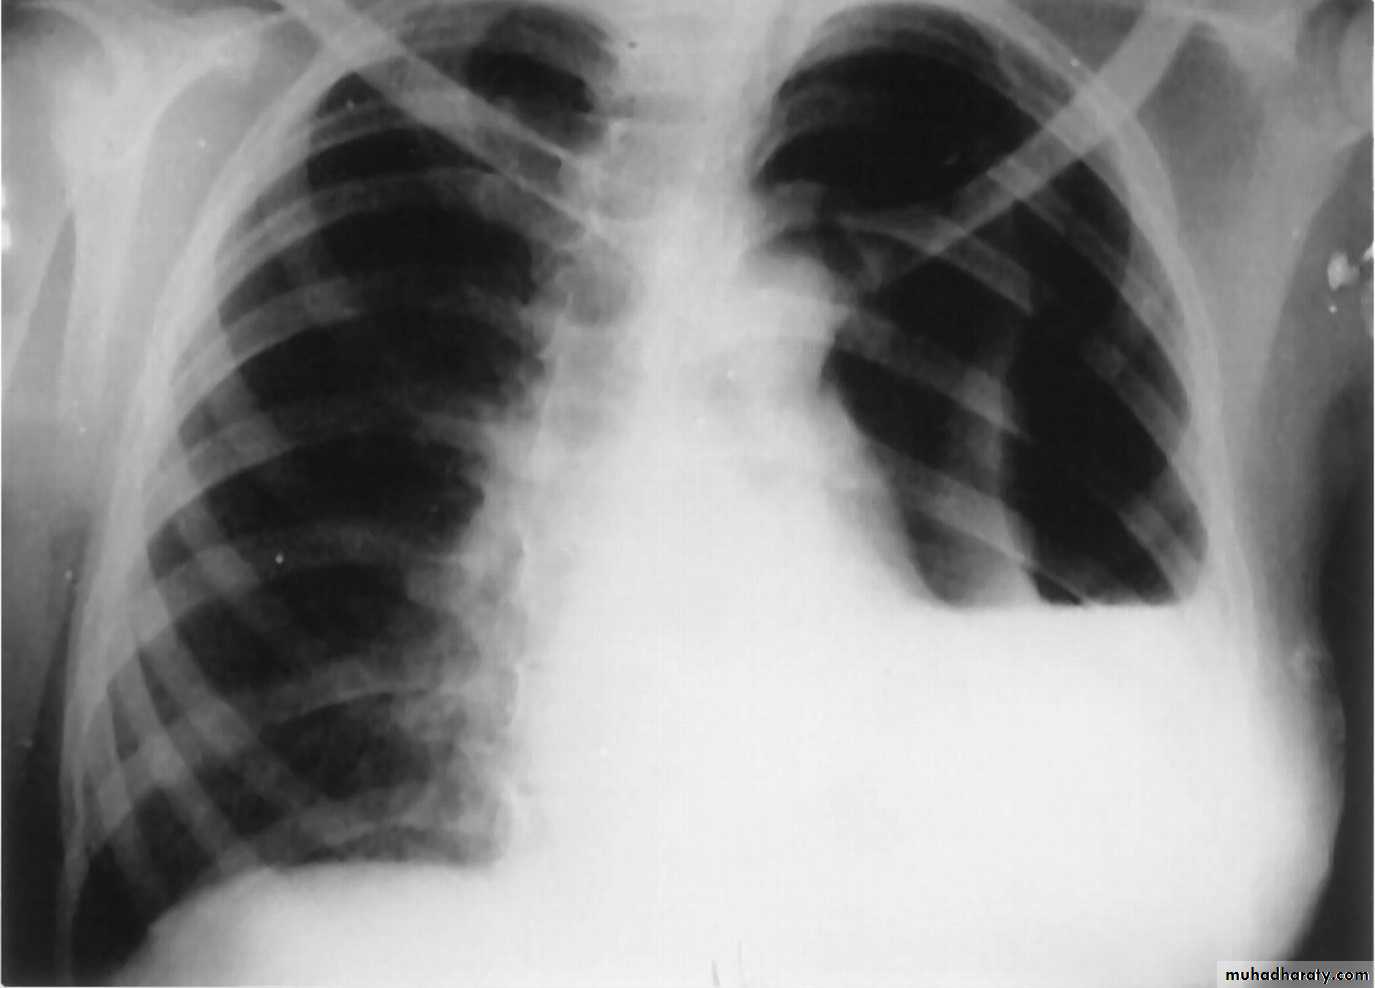

• What immediate action you undertake?SLIDE NO. ((12)) Patient sustnained car accident. He has dyspnea, absence of breath sounds in the left side

• Diagnosis

• Your action• Indication for surgery